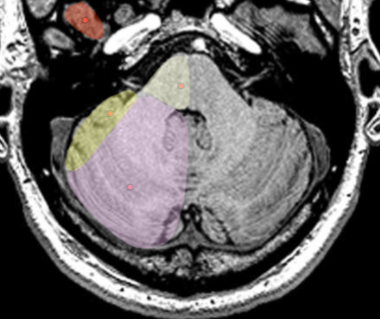

Capsule Interne

- Bras antérieur: Cognition, Emotion, Motivation, Descision

- Genou: Cortico-bulbaire (moteur visage et cou)

- Bras postérieur: TCS (devant) et Sensitif (derrière)

Genou Bras antérieur postérieur homonoculus